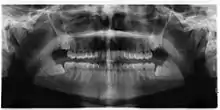

Impacted 2nd molar (red arrow) with developing wisdom tooth (green arrow)

There is no standard to screen for wisdom teeth. It has been suggested, absent evidence to support routinely retaining or removing wisdom teeth, that evaluation with panoramic radiograph, starting between the ages of 16 and 25 be completed every 3 years. Once there is the possibility of the teeth developing disease, then a discussion about the operative risks versus long-term risk of retention with an oral and maxillofacial surgeon or other clinician trained to evaluate wisdom teeth is recommended. These recommendations are based on expert opinion level evidence.[19] Screening at a younger age may be required if the second molars (the "12-year molars") fail to erupt as ectopic positioning of the wisdom teeth can prevent their eruption. Radiographs can be avoided if the majority of the tooth is visible in the mouth.